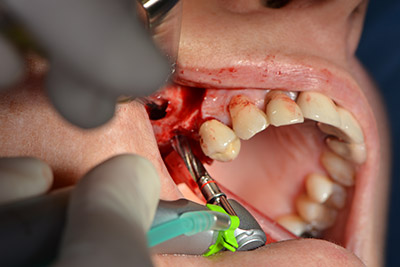

The classic incision (crestal, buccal relief) and the preparation of the mucoperiosteal flap enabled a good overview.

Sky implants (bredent) were used this case. The surgical protocol of these, specify pilot drilling at about 1200 rpm (Fig. 9).

The following holes were drilled at a reduced speed of 300 rpm. The Implantmed demonstrated its true capability at this stage. The surgical protocol can be preset – the various positions can be selected simply by pressing the “P” position of the foot control (Fig. 10 to 11).

The next step was the sinus floor elevation with simultaneous implantation. The Implantmed also had a presetting at the first position for the buccal fenestration of the maxillary sinus wall.

The fenestration was prepared at 35,000 rpm and then the nasal mucosa were prepared in the cranial direction (Fig. 13 to 14).